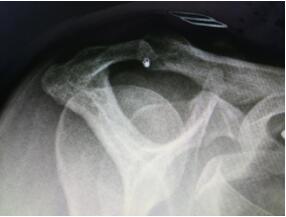

X片检查发现患者为三型肩峰